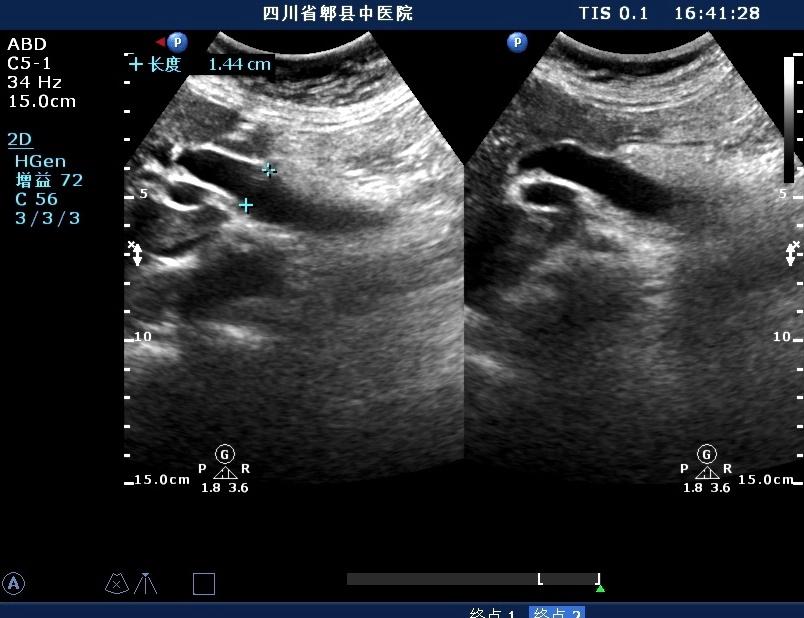

女,70岁,外伤入院就诊,皮肤未见明显黄疸,自述胆囊已切除

超声如图:胆总管及肝内胆管扩张,呈“平行管征”,胆总管胰腺段可见疏松强回声团堆积,后方可见淡淡声影,左肝外叶胆管内亦可见数个强回声团堆积,后方伴声影。 肝脏及胆总管

扩张的胆总管